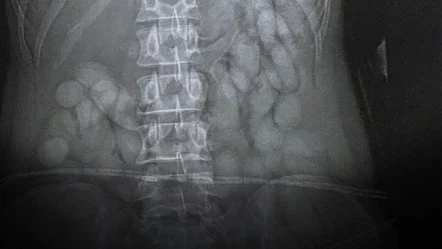

Braziliyanın San-Paulu şəhərindən Yohannesburq Beynəlxalq Hava Limanına gələn 30 yaşlı Namibiyalı qadın polis tərəfindən saxlanılıb. Adı açıqlanmayan qadın narkotik alverində ittiham olunub. Qadının polis əməkdaşları tərəfindən yerli xəstəxanaya çatdırılması və rentgen çəkilişi zamanı həqiqət üzə çıxıb.

Məlum olub ki, qadının üzərində ümumi çəkisi təxminən 850 qram olan 68 paket narkotik vasitə olub. Cənubi Afrika Polis Xidmətinin Milli Komissarı General Fannie Masemola mövzu ilə bağlı aşağıdakı açıqlamanı verib: